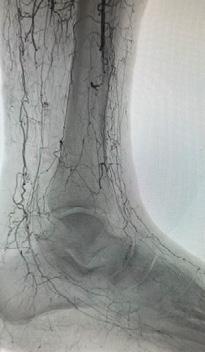

Ons lichaam beschikt over bloedvaten die zuurstof en voedingsstoffen naar onze organen en ledematen brengen. Bij kritieke ledemaatischemie zijn de bloedvaten in het been — vooral de slagaders — zo zwaar aangetast door aderverkalking dat er nauwelijks nog zuurstofrijk bloed in de voet komt (Figuur 1). Dat veroorzaakt pijn in rust of ‘s nachts en wondjes die niet genezen. Zonder behandeling ontstaat weefselversterf (gangreen), met een verhoogd risico op infectie, amputatie en overlijden.

Bij de meeste patiënten kunnen we de doorstroming verbeteren. Afhankelijk van de ernst en de locatie van deze verstoppingen kiezen we voor een ballondilatatie (Percutane Transluminale Angioplastiek of PTA) of een overbruggingsoperatie (bypass) (Figuur 2a en b). Bij een kleine groep patiënten – vaak met diabetes en/of chronisch nierlijden – zijn de bloedvaten in het onderbeen en de allerkleinste vaatjes in de voet zo ernstig verstopt dat klassieke technieken geen haalbare optie zijn.

GEBLOKKEERDE SLAGADER

Bij diep veneuze arterialisatie (DVA) draaien we als het ware het systeem om. In plaats van het bloed via slagaders (arteries) naar de voet te brengen, leiden we het zuurstofrijke bloed rechtstreeks in de diepe aders (venen) van het onderbeen en de voet. Normaal brengen deze aders het bloed terug naar het hart, maar na deze ingreep kan zuurstofrijk bloed via dit netwerk naar de voet stromen en zo de weefsels opnieuw voeden. Het doel? Wondgenezing stimuleren en amputaties vermijden, zelfs als er geen arteriële doorgangen meer beschikbaar zijn.

Diep veneuze arterialisatie is geen standaardbehandeling, maar een laatste redmiddel voor patiënten waarbij alle klassieke opties zijn uitgeput. Door middel van deze ingreep proberen we een amputatie van het onder- of bovenbeen te vermijden. Voor de procedure onderga je een grondig preoperatief onderzoek om te bepalen of veneuze arterialisatie geschikt is voor jouw specifieke situatie.

De procedure vindt plaats in onze hybride operatiezaal onder algemene verdoving. Via kleine prikken in de lies en de voet worden een slagader en een diepe ader met elkaar verbonden — dit noemen we een arterioveneuze (AV) fistel. Vervolgens plaatsen we een stent die het bloed richting voet leidt (Figuur 4, voor en na).

Na deze eerste ingreep heeft het lichaam tijd nodig om zich aan te passen. Gedurende 6 à 8 weken volgt een rijpingsproces waarbij het aderlijk netwerk zich verder ontwikkelt en connecties maakt met het slagaderlijk netwerk (Figuur 5, voor en na). Tijdens deze periode doen we regelmatige controles middels echografie om te beoordelen of de nieuwe doorstroming goed functioneert. Meestal is nog een tweede ingreep nodig om kleine zijtakjes af te sluiten, zodat het bloed verder richting de voet kan worden gestuurd.

Nauwkeurige opvolging is dus cruciaal. We combineren medische beeldvorming met gespecialiseerde wondzorg. Vaak is een beperkte ingreep nodig om afgestorven

weefsel (bv. een teen of een deel van de voet) te verwijderen. Deze kleine amputatie wordt meestal pas uitgevoerd wanneer de bloedvoorziening voldoende hersteld is — ten vroegste 6 à 8 weken na de DVA.

Genezing van chronische voetwonden duurt vaak maanden, maar het belangrijkste is dat we bij ongeveer 60 tot 70% van de patiënten een amputatie van het onder- of bovenbeen kunnen voorkomen. DVA is geen ‘mirakeloplossing’, maar biedt wél hoop voor patiënten bij wie klassieke ballondilatatie/stent of bypass tot voor kort geen uitweg meer bood.